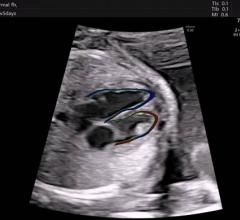

April 01, 2021Here are two quick clinical examples of point-of-care ultrasound (POCUS) lung imaging and cardiac imaging using a GE Vscan Air device. The examples show an abnormal lung image with B-lines. The second clip shows a healthy heart in a parasternal color Doppler image.

The GE Healthcare Vscan Air is a cutting-edge, wireless pocket-sized ultrasound that provides crystal clear image quality, whole-body scanning capabilities, and intuitive software. The pocket-sized ultrasound system was originally introduced in 2010, and as of early 2021, there are over 30,000 Vscan systems in use. The new Vscan Air features a wireless ultrasound probe.